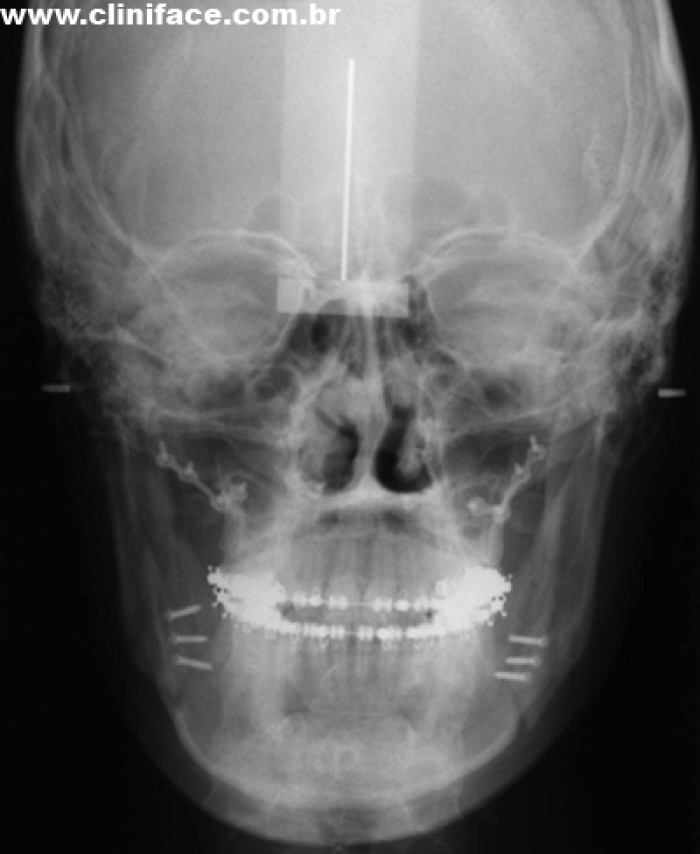

Telerradiografia frontal inicial